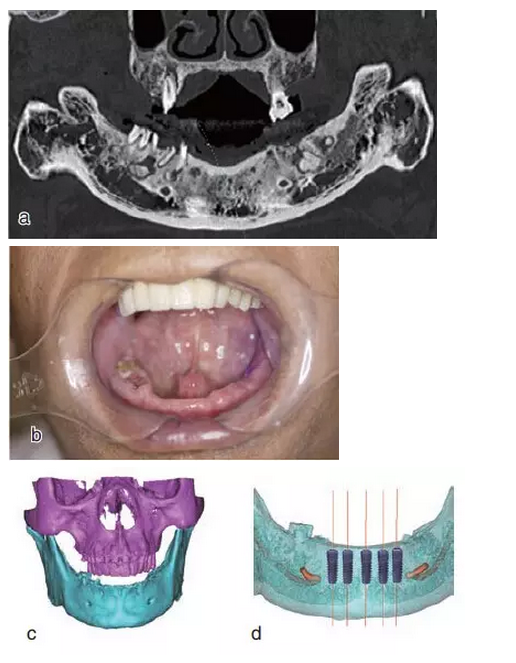

本案例為78歲男性患者,下頜義齒活動(dòng)、固位差,口內(nèi)有殘根。患者要求進(jìn)行種植義齒修復(fù)。

術(shù)前拍攝錐形束CT,進(jìn)行三維重建和種植方案規(guī)劃。從CT圖像中可以看出頜骨內(nèi)有骨島和殘根,為避免種植體植入骨島區(qū),考慮在兩側(cè)頦孔區(qū)種植4~5顆種植體,采用套筒冠進(jìn)行即刻修復(fù)。從重建的結(jié)果中可知前牙區(qū)牙槽嵴呈刀刃狀。種植方案為:對前牙區(qū)牙槽嵴進(jìn)行截骨修整,并在兩頦孔之間的區(qū)域內(nèi)植入5顆種植體。

圖15

種植方案的規(guī)劃:a.患者的CT圖像的截面圖,圈紅處為骨島;b.患者摘掉活動(dòng)義齒后的下頜;c.患者上下頜骨的CT三維重建;d.下頜骨截骨后模擬植入5顆種植體